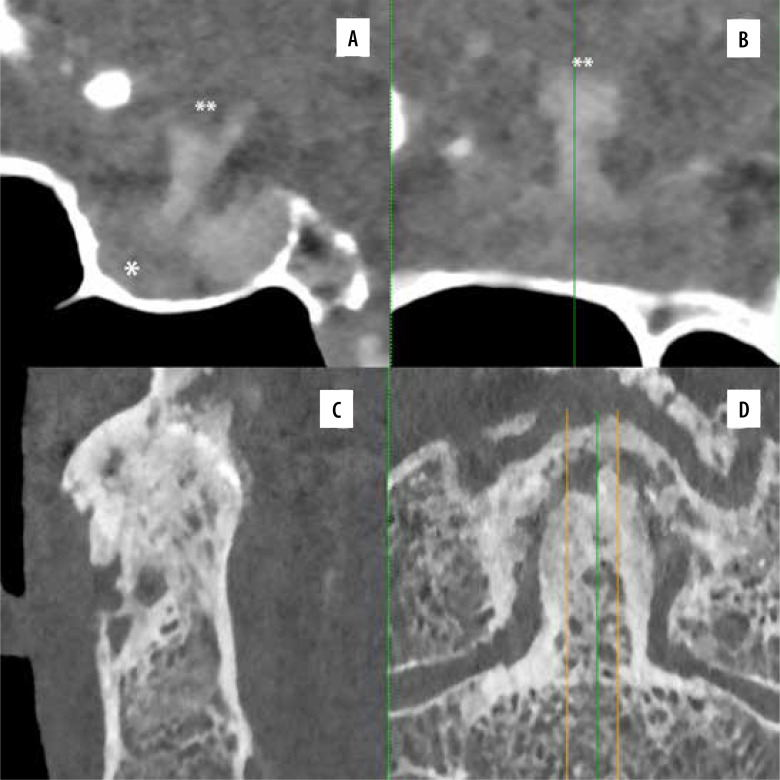

Photon-counting detector computed tomography (PCD-CT) devices have recently been introduced into practice, despite photon-counting detector technology having been studied for many years. PCD-CT devices are expected to provide advantages in dose reduction, tissue specificity, artifact-free imaging, and multi-contrast demonstration capacity. Noise reduction and increased spatial resolution are expected using PCD-CT, even under challenging scanning conditions. Some experimental or preliminary studies support this hypothesis. This pictorial review illustrates the features of PCD-CT systems, particularly in the interventional field. PCD-CT offers superior image quality and better lesion discrimination than conventional CT techniques for various conditions. PCD-CT shows significant improvements in many aspects of vascular imaging. It is still in its early stages, and several challenges have been identified. Also, PCD-CT devices have some important caveats. The average cost of these devices is 3 to 4 times higher than conventional CT units. This additional cost must be justified by improved clinical benefits or reduced clinical harms. Further investigations will be needed to resolve these issues.